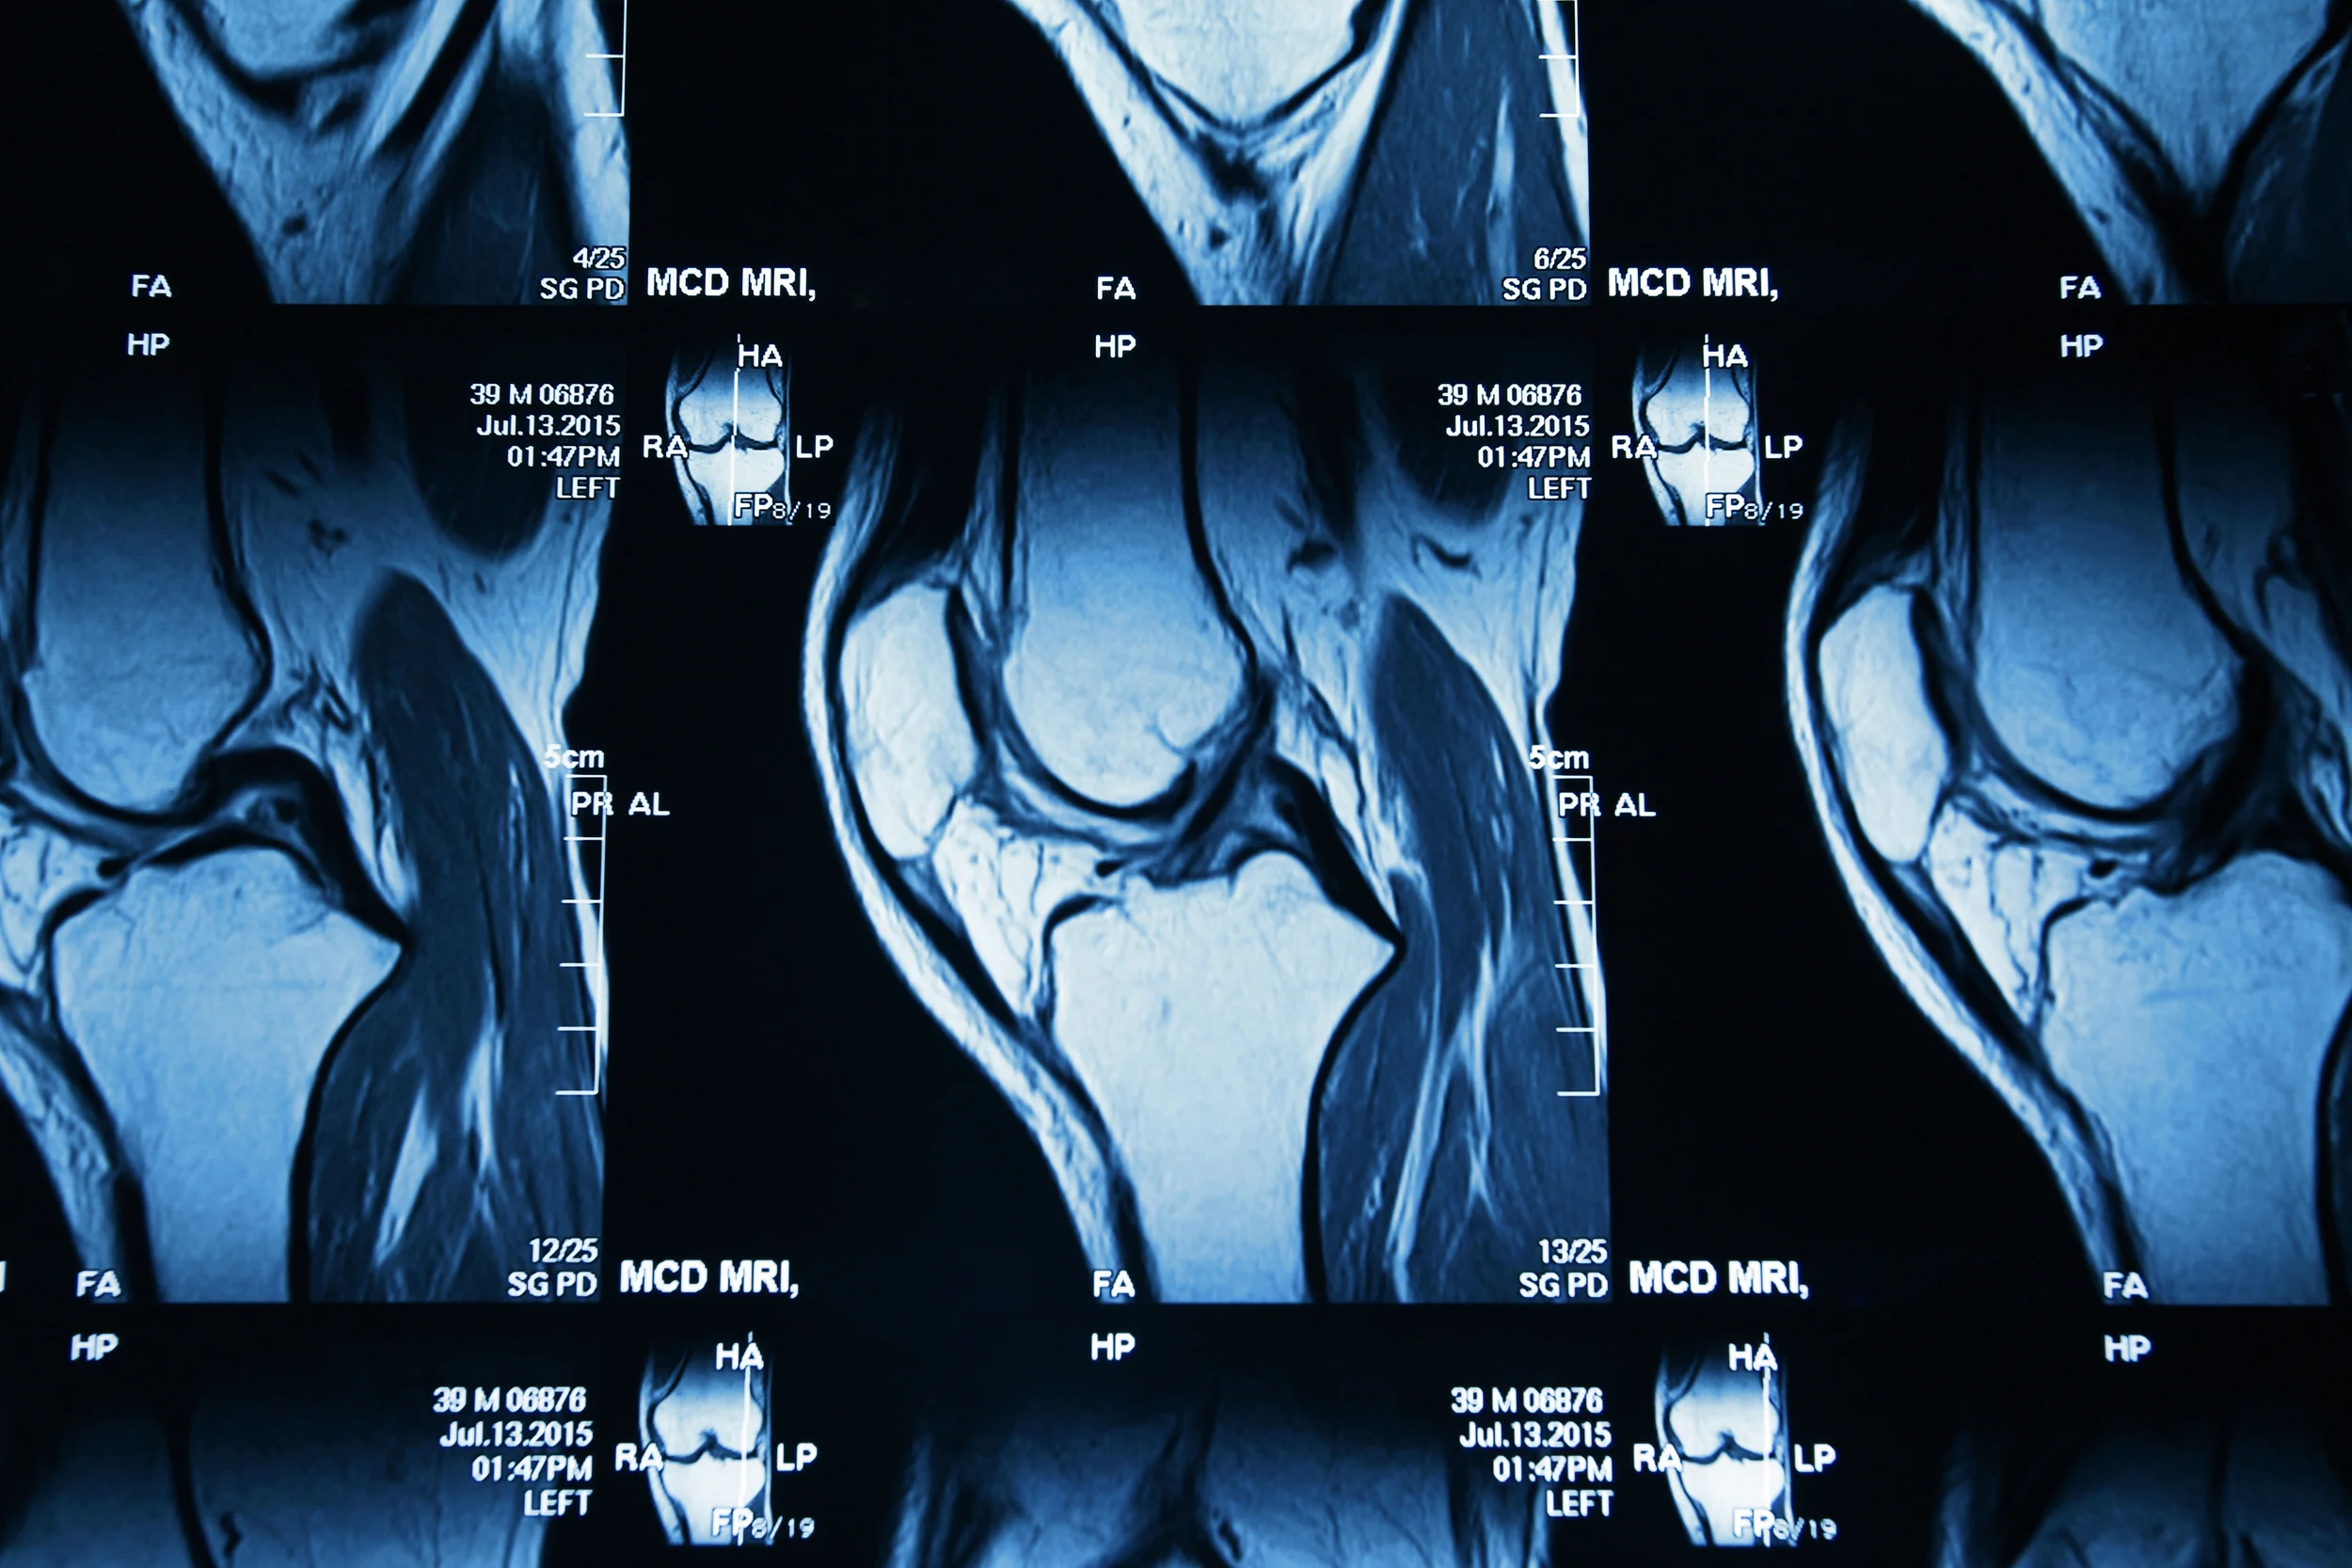

Si tratta di una chirurgia che offre la possibilità di sostituire un'articolazione dolente e funzionalmente limitata per usura o per traumi, ripristinando una funzione quasi del tutto normale. E' indicata per tutti coloro che hanno usurato il ginocchio. Le cause sono molteplici: alcuni per predisposizione genetica, altri per l'età, qualcuno per il lavoro svolto negli anni, altri ancora per traumi subiti in passato. Interessa tutti coloro, per intenderci, che in età adulta hanno problemi nella vita di tutti i giorni. La chirurgia protesica consta di diversi passaggi: si può eseguire, per esempio, una protesi totale, parziale o addirittura optare per una mini protesi a seconda dell'usura dei componenti dell'articolazione. La scelta di optare per una specifica soluzione è data da diverse variabili a discrezione del chirurgo: dall'ampiezza del danno, dall'età e dal peso del paziente e dal fatto che il ginocchio possa avere un asse più o meno corretto.

Non esiste un vademecum specifico per prevenire le patologie del ginocchio. Sicuramente può essere utile evitare gli eccessi (evitando, per esempio, la pratica di sport in maniera estrema), mantenere un peso forma ideale, stare attenti all'alimentazione, prestare attenzione ai sintomi, rivolgersi a personale medico competente. La prevenzione è importante anche per la correzione delle alterazioni meccaniche evidenti in età giovanile (soprattutto valgismo costituzionale grave, ginocchia ad x per intenderci) e quelle determinate dalle lesioni capsulo-legamentose (rottura del Legamento Crociato Anteriore in primis) che alterando la biomeccanica provocano movimenti anomali ed un’usura precoce.